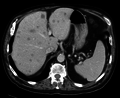

Tests include a blood test to look for raise liver enzymes.[1] Ultrasound, CT scan, MRI scan and PET scan are used to investigate the origin of the cancer and to define the extent of disease.[1][4] Taking a sample of liver tissue, guided by medical imaging, may confirm the diagnosis.[2] Treatment generally involves treating the original cancer and cutting out parts of affected liver.[1][4] Other therapies include chemotherapy, radiofrequency ablation, thermal therapy and cryotherapy.[1] Medicines such as bevacizumab and cetuximab and immunotherapeutic agents, may be other options.[4] The choice of treatment and the outcome may be guided by genetic tests.[4]

Tests include a blood test to look for raise liver enzymes.[1] Ultrasound, CT scan, MRI scan and PET scan are used to investigate the origin of the cancer and to define the extent of disease.[1][4] Taking a sample of liver tissue, guided by medical imaging, may confirm the diagnosis.[2]